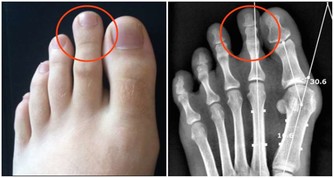

腎病

整個面色黎黑垢濁,下眼瞼腫,色黑,為腎久病。